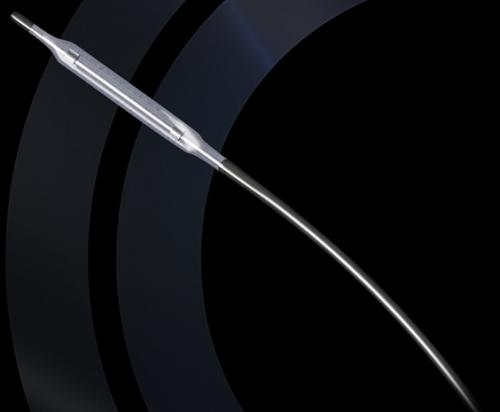

GOVT CATHETER BALLOON DS 10X20MM 7FR DILATATION 80CM

Item #:

420005

Manufacturer Item: 4150020S

Manufacturer:

CORDIS

UNSPSC: 42203405